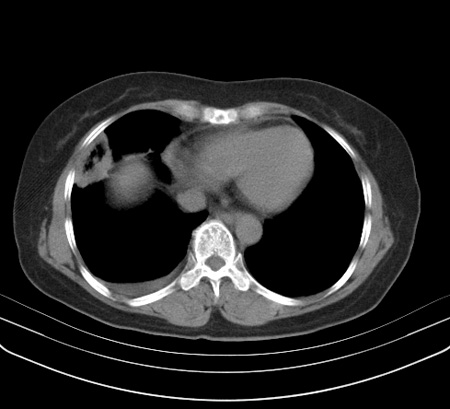

以下是引用余辉在2009-2-19 20:10:00的发言:[br]多考虑急性感染性病变,右中叶尚可见多枚小斑片状影,多为化脓性肺炎,双侧胸腔积液

以下是引用随光逐影在2009-2-19 20:33:00的发言:[br]1)考虑右肺炎症;建议抗炎治疗后复查。2)双侧胸腔积液(以右侧为甚)。

以下是引用花凤凰在2009-2-19 20:46:00的发言:[br]病人有发热,胸痛急性起病,主要病变位于右肺中叶外侧段,呈楔行改变,位于外带胸膜下,考虑为肺梗塞可能!!!!!!!!!!!!!!!!!!!!!!!!!!!!!!!!!!!